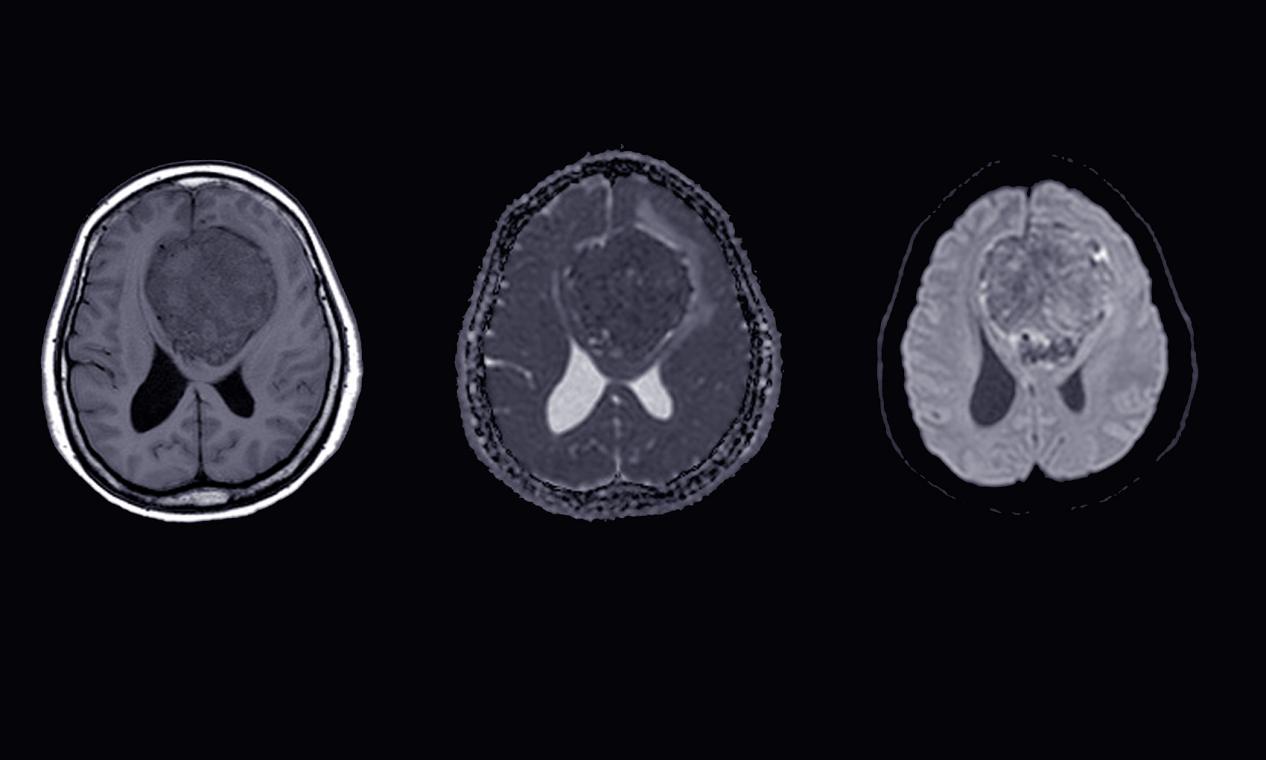

腦膜瘤是一種危險(xiǎn)的腦部腫瘤,治療需要綜合考慮患者的個(gè)體情況和病情,通常需要多種治療方法的組合應(yīng)用。以下是達(dá)州治療腦膜瘤的一些常用方法: